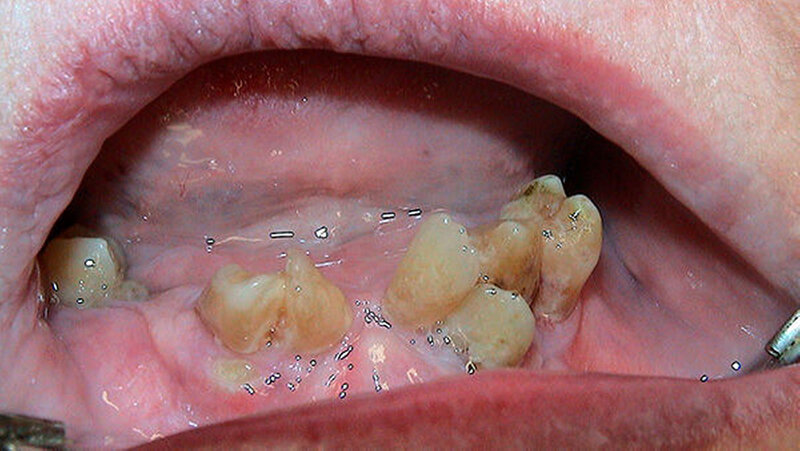

Er schreibt: "Als eine Patientin unsere Praxis aufsuchte, um sich im Notdienst ihre frakturierte totale Oberkieferprothese reparieren zu lassen, so war dies an sich noch kein spektakuläres Ereignis (Abbildung 1). Doch als sie gebeten wurde, auch ihre subtotale Unterkieferprothese mit Drahtklammerfixierung am teil-retinierten Zahn 47 zum Zwecke einer eingehenden Inspektion der Mundhöhle zu entfernen, reagierte sie merkwürdig zögerlich, unwillig und peinlich berührt. Erst nach eindringlicher Bitte gab sie nach und entfernte den Zahnersatz (Abbildung 2).

Es ergab sich ein absolut überraschendes und in dieser Form sicherlich einmaliges Bild: Sowohl im Ober- als auch im Unterkiefer befanden sich durchgebrochene, zum Teil gekippte Zähne, die topografisch nur schwer zuzuordnen waren und von dem eingegliederten Zahnersatz vollständig bedeckt wurden (Abbildungen 3 und 4).